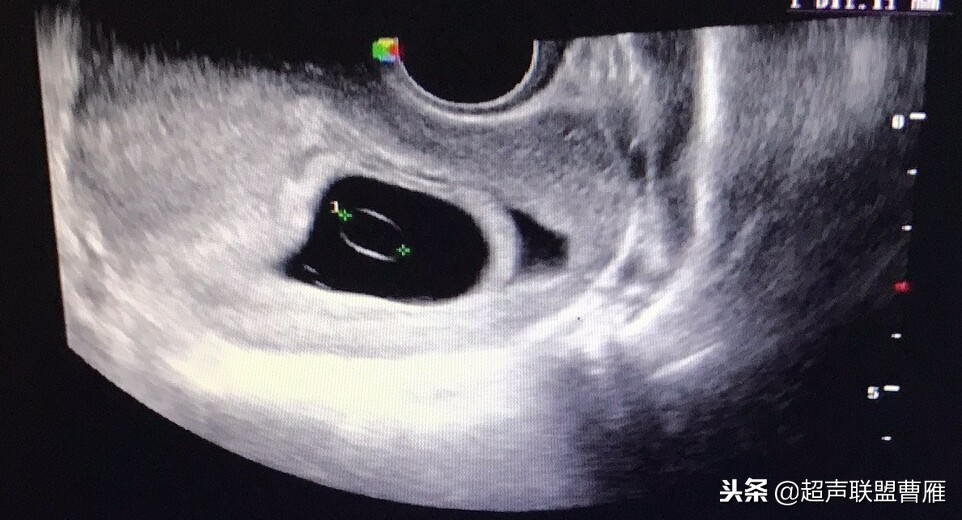

妊娠37天超声检查卵黄囊可以显示,羊膜腔及胚胎不能显示

真实的卵黄囊、胚体及羊膜腔形象

妊娠37天出现卵黄囊

在妊娠妊娠38天前后(36-40)天可以见到卵黄囊。 孕囊在6-9mm的可以见到其中有卵黄囊。

HCG在1000-7200U/L之间可以见到卵黄囊的近50%。 HCG在7200U/L以上都能见到卵黄囊。

有的图像卵黄囊YS只是两条平行的细短线

妊娠40天,见到卵黄囊、胚极及心管搏动, HCG12800U/L。

妊娠35天,高分辨的超声检查就可能见到心管搏动、胚极及卵黄囊。

卵黄囊高分辨超声图像,妊娠40天